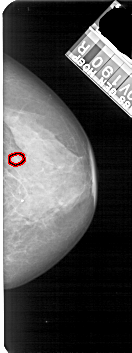

FILE: A_1683_1.RIGHT_CC.OVERLAY

TOTAL_ABNORMALITIES 1

ABNORMALITY 1

LESION_TYPE MASS SHAPE OVAL MARGINS OBSCURED

ASSESSMENT 3

SUBTLETY 3

PATHOLOGY BENIGN

TOTAL_OUTLINES 1

BOUNDARY